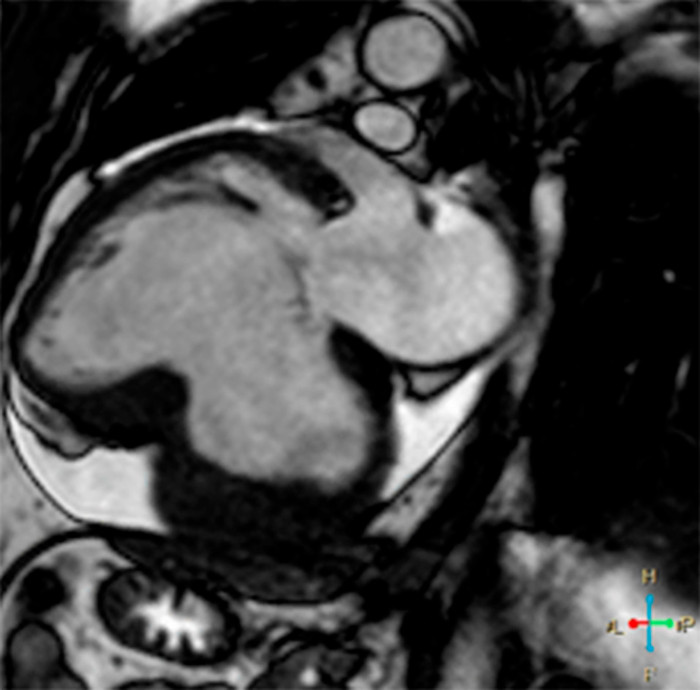

Se presenta el caso de un paciente de sexo masculino, de 50 años de edad, derivado por infarto agudo de miocardio de cara inferior, 25 días previos a la consulta, no habiendo sido revascularizado. Se encontraba clínicamente estable. Debido a presentar mala ventana acústica, se solicita la realización de una resonancia magnética cardíaca con contraste no ferromagnético (gadoterato de meglumina). Bajo esta técnica, se observa una cavidad en comunicación con la cámara ventricular izquierda, de cuello ancho y la presencia en su interior de un trombo que tapiza su superficie (Fig. 1, dos cámaras y Fig. 2, eje corto). Tras la administración del contraste, se observa realce tardío a los 10 minutos de la pared de esta estructura (Fig. 3, eje corto), certificando la naturaleza aneurismática y descartando el pseudoaneurisma ventricular. Debido a su tamaño, ante la posibilidad de desarrollo de falla cardíaca o evento embólico, se decide su intervención quirúrgica para plástica ventricular certificando la anatomía patológica la naturaleza fibrótica de su pared.